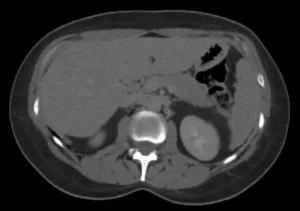

Fase nefrográfica

Fase excretora

Imagens-chave

Derivação urinária em alça delgada na fossa ilíaca à esquerda. Houve boa distensão da alça de derivação, porém nota-se falha de enchimento de aspecto polipoide na fase excretora medindo cerca de 2,2 x 1,0 cm. Sugere-se prosseguir investigação.

• Lesão polipoide na alça ileal da derivação urinária